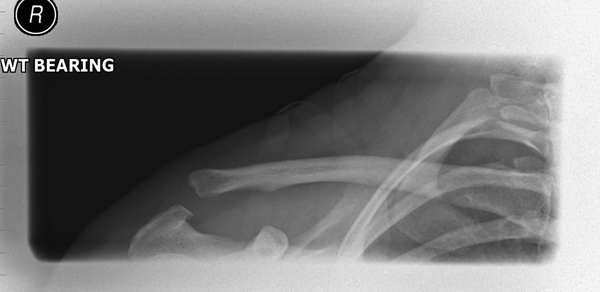

What is a step off deformity and what injury would you see it with?

elevation of the clavicle

AC joint separation

How do you appropriately grade acromioclavicular separations?

XRAY is taken with the person holding a weight to assess the level of injury to the joint

Management of AC joint separation

Conservative management is possible for mild to moderate injuries because they can be managed with sling and analgesia

more severe injuries will require operative repair